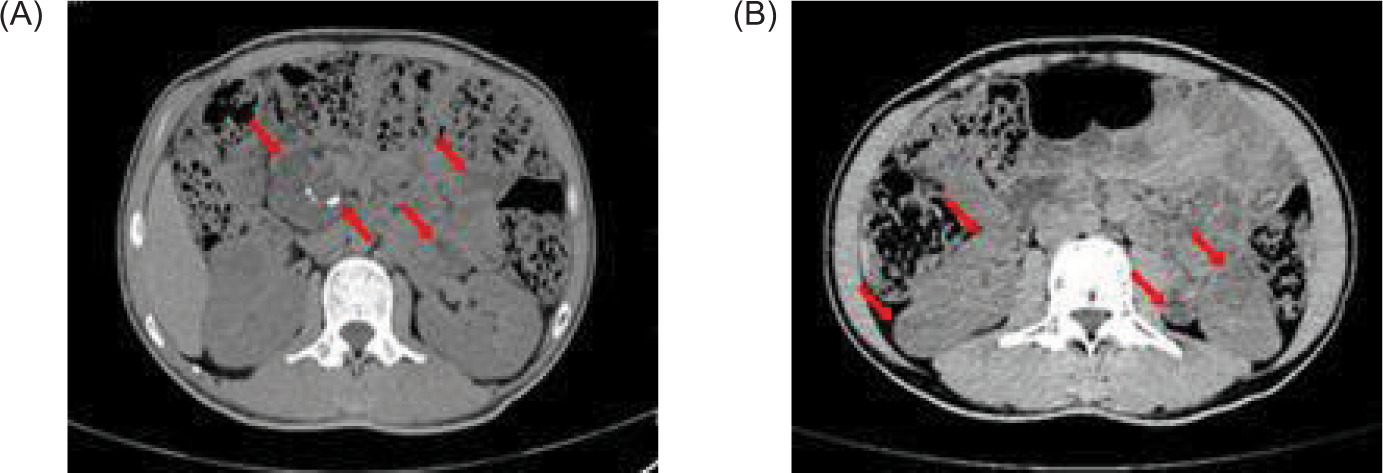

Full abdominal CT and lung CT revealed a high-risk pulmonary nodule in the right lower lobe (Figure 4), pancreatic enlargement with multiple cystic lesions, and multiple ill-defined low-density lesions in both kidneys (Figure 5).

Figure 5: Full abdominal CAT (CT) scan shows pancreatic enlargement with (A) multiple cystic foci and scattered calcification in the pancreas (red arrow), and (B) multiple low-density nodules in the kidney (red arrow).